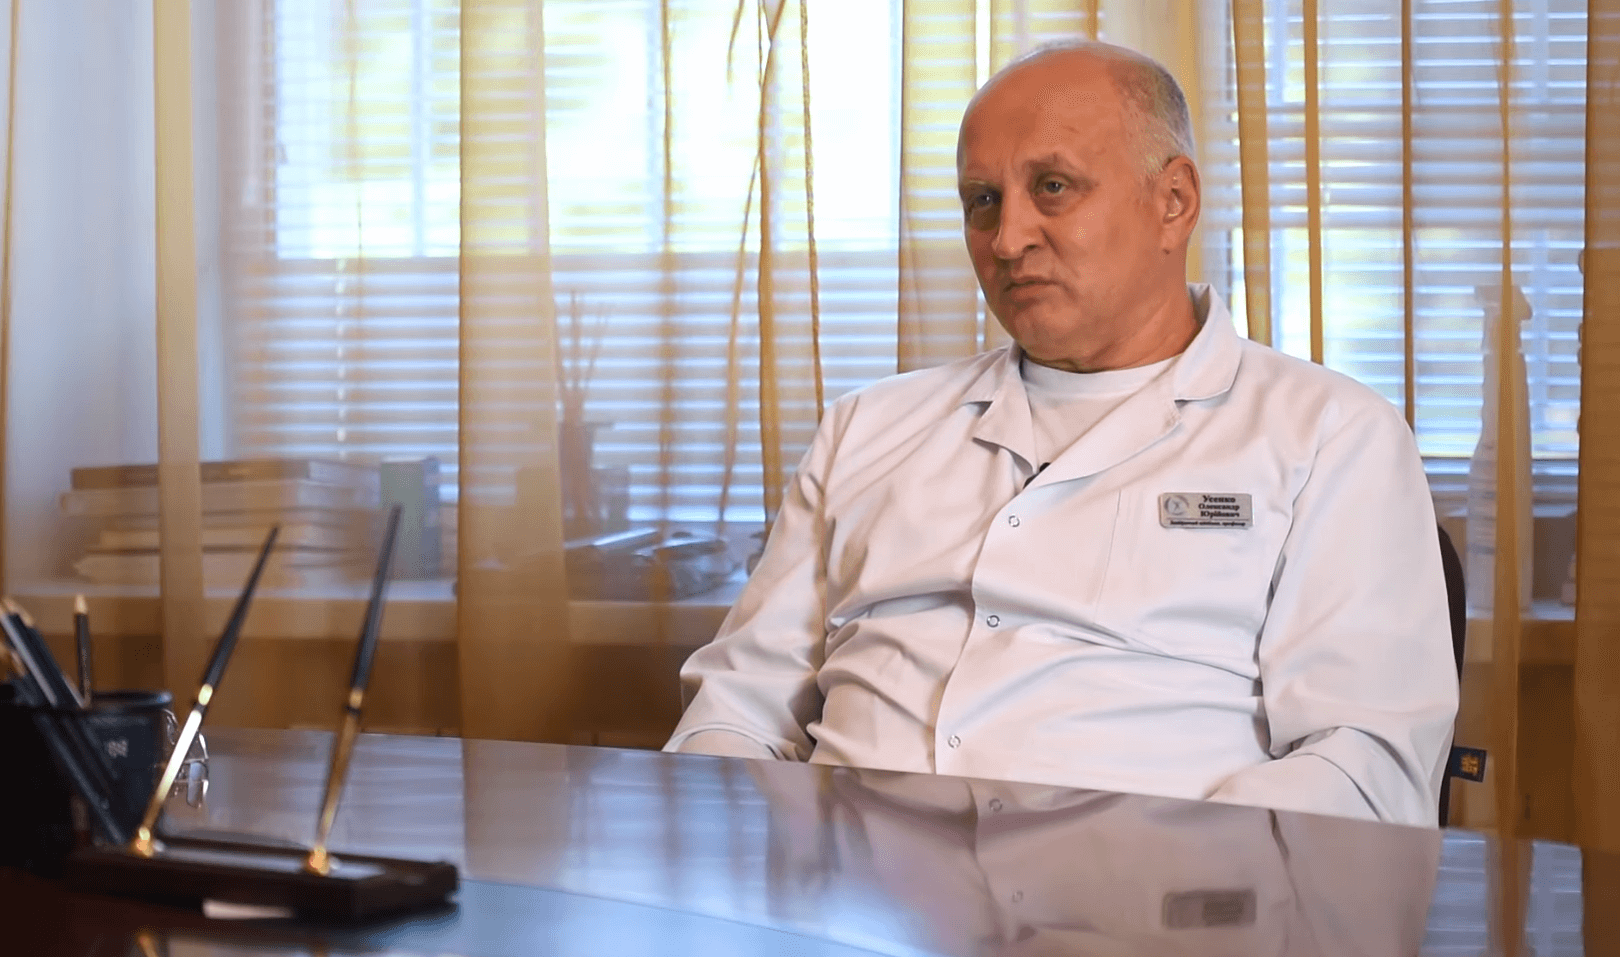

Відповідає: Усенко Юрій Іванович - професор, президент міжрегіональної громадської організації «Наукове співтовариство зі сприяння клінічному вивченню мікробіома людини» (НСОІМ).

— Юрію Івановичу, чи правда, що звичайний запор призводить до раку органів шлунково-кишкового тракту?

— Чи можна на ранніх стадіях запобігти хворобі?

— Але що буде, якщо взагалі нічого не робити та не лікувати це захворювання?

— Напрошується питання: «Чому ж вчені не можуть розробити нові ефективні засоби чи використовувати західну систему відновлення шлунково-кишкового тракту?»

— Нам відомо, що Санацин немає в аптеках. І лікарі його не призначають. Чому?

— Юрію Івановичу, так звісно ми будем тільки раді допомогти людям. Дякую за інтерв'ю! Бажаєте ще щось сказати нашим читачам?